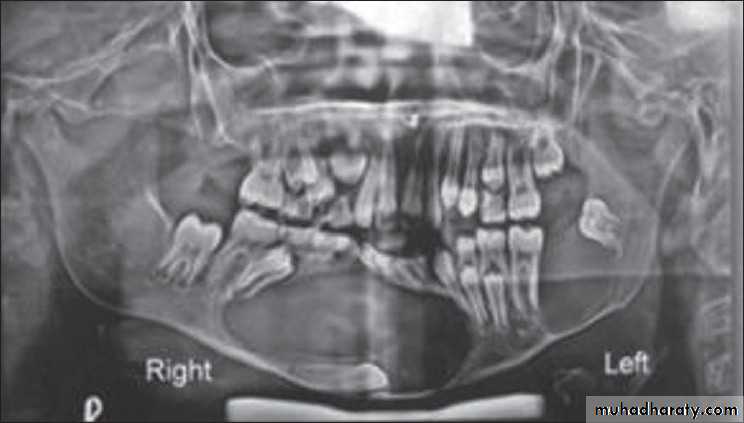

A 11-year-old female with swelling on the right side.

impacted canine

Odontogenic keratocyst:*This cyst develops from the epithelium of the dental lamina instead of the normal tooth which is therefore typically missing from the series.

*The regional teeth are vital.

*Shape: Oval, extending along the body of the mandible with little

mediolateral expansion.

*Minimal displacement of the adjacent teeth , rarely resorbed

Extensive expansion within the cancellous bone.

*Treatment by surgical excision.